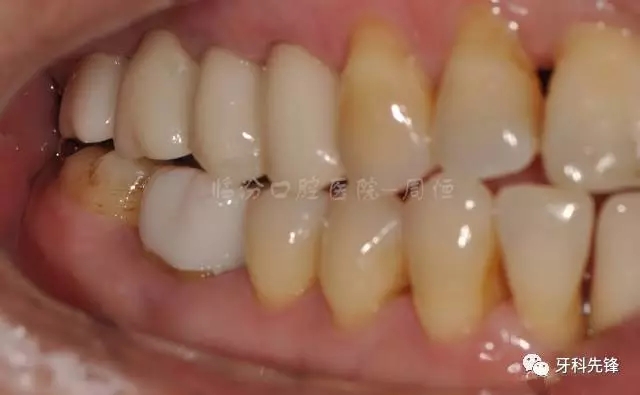

圖5拆除原修復體側位咬合照

640.webp (6).jpg